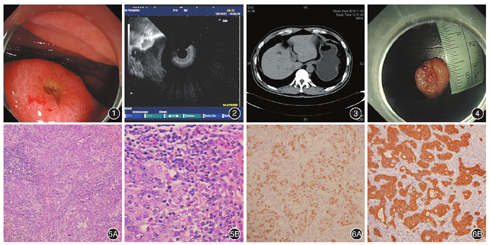

患者男,53岁,以"反复中上腹闷痛7个月"行胃镜检查,见胃体大弯上段一火山样隆起型病变,中央凹陷,表面见少许白苔,大小约1.0 cm,边界尚清(图1)。多次活检病理均提示:急慢性炎症细胞浸润,幽门螺杆菌(+)。既往史:发现乙肝病毒携带十余年。EUS:病灶源于黏膜下层,呈不均匀偏低回声,呈分叶状,边界尚清,紧临肌层,肌层尚完整,考虑黏膜下肿物可能(图2)。上腹部CT增强:胃底体交界处稍不规则增厚,最厚约0.8 cm,略呈结节样;邻近肝胃间隙小淋巴结;考虑:炎症(?),间质瘤(?),异位胰腺(?)(图3)。为进一步明确病灶性质,行诊断性ESD,标本大小约1.5 cm×1.5 cm(图4)。术后病理诊断:胃淋巴上皮瘤样癌(lymphoepithelioma-like gastriccarcinoma,LELC),侵及黏膜下层,标本周切缘及底切缘均未见癌残留,无神经及脉管侵犯。术后病理学及免疫特点:肿瘤呈圆盘状,中央凹陷,最大直径1.5 cm,灰褐色,质地稍硬,无包膜。镜检可见在大量淋巴细胞的背景下,瘤细胞呈团状、巢状、条索状分布(图5A)。癌细胞呈圆形、椭圆形或梭形,呈丰富嗜酸性,核膜厚,分裂像少见,染色质呈空泡状,部分可见明显核仁,浸润性淋巴样细胞(包括小淋巴细胞、少量转化样淋巴细胞及浆细胞,图5B)明显多于瘤样细胞,部分可见淋巴滤泡形成,异形淋巴细胞少见,间质胶原纤维蛋白成分较少。免疫组化:Ki-67(60%+),CK18(+++),CD56(-),P63(-),CgA(-),SY(-),ck(pan)(+++),EBER(+)。肿瘤细胞CK18、ck(pan)阳性,提示来源于上皮来源,并采用原位杂交的方法检测出EB病毒编码的小RNA(EBER+)(图6A),阳性定位在肿瘤细胞核中(图6B),而周围胃黏膜及淋巴样细胞阴性。手术治疗及随访:考虑到特殊类型的胃癌及侵犯黏膜下层,患者及其家属考虑行根治性全胃切除术(D2),术后病理:部分区域黏膜缺失,间质纤维、肌纤维母细胞增生,找到周围25枚淋巴结,未见转移灶。2个月后复查全身PET-CT未见肿瘤复发及转移征象。目前仍在随访中。

胃LELC以黏膜下肿物的形式表现较为少见,本例中在白光内镜下表现为盘状隆起,中央凹陷,超声内镜提示偏低回声的黏膜下肿物,肌层完整,无液化、坏死等征象,且剥离过程中病灶与肌层明显粘连,剥离血管丰富易出血。但术后病理及免疫组化提示胃淋巴上皮瘤样癌。该病变好发于老年男性,临床上常表现为腹部不适、反酸、胀痛、呕血等,绝大数表现为近期症状加重,但是消化道症状无明显特异性。典型的内镜下表现为隆起型病变,中央伴有凹陷、浅溃疡形成,边界清晰[4]。由于肿瘤表面覆盖正常黏膜,内镜常规活检通常无法取到癌组织,超声内镜可以清楚显示病灶性质、大小、起源和与周围关系,但是超声内镜下常表现为黏膜下肿物,常无法与其他常见的黏膜下肿物鉴别。对于CT检查,能判断病灶性质、位置及淋巴结转移情况,虽然不能明确诊断,但是对后续的治疗有进一步指导的意义。胃LELC术前诊断困难,主要依靠病理组织学及免疫组化确诊,进行EBER原位杂交试验是关键,如果阳性,可确诊为胃LELC[5]。该病的主要特点是肿瘤内部含有丰富的淋巴样间质细胞,边界不规则,呈浸润生长,是一种罕见的具有特殊临床病理学特点的低分化腺癌。在大量淋巴细胞的背景下,瘤细胞呈团状、巢状、条索状分布。利用原位杂交的方法检测出定位在肿瘤细胞核中的EBER,而周围胃黏膜及淋巴样细胞阴性。本研究中采用原位杂交的方法在癌组织中检测到了EBV编码的小RNA,从而考胃LELC可能与EBV感染有关。有研究表明,EBV感染胃黏膜上皮细胞,使许多癌症相关基因(p16、p73、E-cadherin等)的启动区GpC岛发生甲基化而表达下调,最终导致肿瘤的发生[6]。